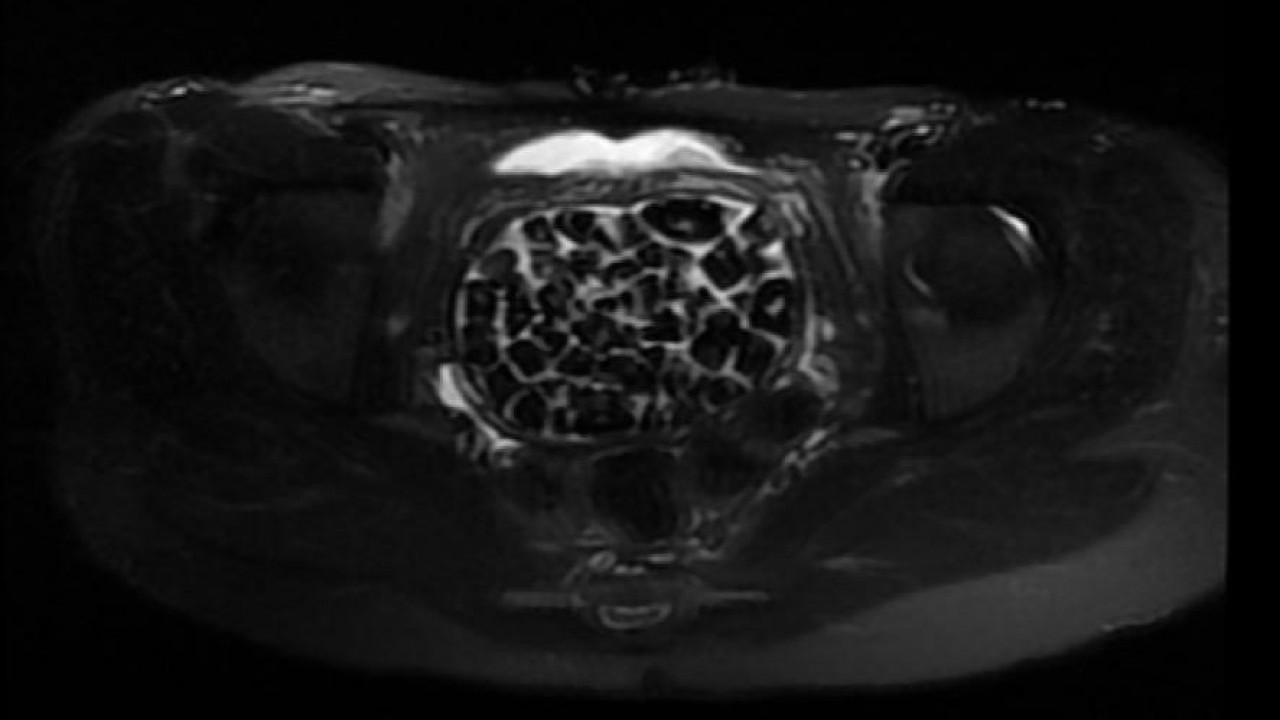

287 taş hem doktorları hem hasta ve ailesini şok etti Genç kızın ameliyat işlemleri başlatılırken 11 Eylül’deki operasyon sırasında doktorlar da şaşkınlık yaşadı. Öztürk’ün vücudundan 287 adet çeşitli ölçülerde taş çıkarılırken üroloji ve jinekolojik onkoloji ekibi operasyonu başarıyla tamamladı. Taşların sayısını duyan genç kız ve ailesi şok olurken operasyonun ardından karın ağrıları dinen Öztürk, rahat bir nefes aldı. Tedavisi sonrası taburcu edilen genç kız yaşadıklarını anlatırken, operasyonu gerçekleştiren Üroloji Uzmanı Doç. Dr. Erkan Erkan ile Jinekolojik Onkoloji Uzmanı Op. Dr. Emin Erhan Dönmez de nadir olduğunu ifade ettikleri vakaları hakkında bilgi verdi, önemli uyarılarda bulundu. Öte yandan, genç kızın vücudundaki 287 taşın tetkiklerdeki görüntüsü dikkat çekerken taşlar üzerine de incelemeler yapılacak.

"287 adet taş çıkardık, literatürde çok nadir görülen bir olay" Hastasının durumuna yönelik konuşan Üroloji Uzmanı Doç. Dr. Erkan Erkan, "Hastamızın 2004 yılında doğduğunu ardından doğar doğmaz ekstrofi vezika dediğimiz 50 binde bir görülen bir anomaliden dolayı art arda ameliyatlar geçirdiğini öğrendik. 10 yaşında yine bir ameliyat geçirmişti, gerekli görüntüleme ve tetkiklerimizi yaptırdık. Normalde mesanesinin olması gereken yerin hemen arka kısmında taşlarla dolu bir kese olduğunu gördük, bunun üzerine ek görüntülemeler; MR çektirdik. Hastamız çelişkili açıklamalar almıştı, kendi radyolojik kliniğimiz ve edindiğimiz konsültasyonlarda taşların mesanede değil vajinal boşlukta oluştuğunu düşündük, bir planlama yaptık. Kadın doğum hocamızın da çabasıyla taşları tamamen temizledik ardından ileride normal bir hayat sürmesi bakımından oraya plastik cerrahi yaptık. 287 adet taş çıkardık, pratikte gerçekten görünce çok şaşırdık çünkü bu aynı zamanda literatürde çok nadir görülen bir olay. Biz ameliyata hazırlanırken de teorik olarak biraz araştırdık. Literatürde gördüğümüz kadarıyla buna benzer bu tanıma uyan bir vaka vardı. Literatürde sanırım yayınlanmış 2’nci vaka olacak. Farkındalık çok önemli, bilinçli bir hastamız vardı. Doğumsal anomaliyle doğan çocuklarımızda ileride bunlara bağlı bazı sıkıntılar çıkabileceğinin öngörülmesi lazım. İlgili tedavilerini alsalar bile düzenli takiplere gelmeleri gerekiyor. İleride eğer dikkat etmezse ki zannetmiyorum, tekrarlayabilir. Bu rahatsızlık ekstrofi vezikal epispadias durumu çok nadir bir durum" dedi.

"Tüm vajenin taşlarla dolu olduğunu gördük" Genç kızın uzun süredir devam eden karın ağrısı olduğunu söyleyerek sözlerine başlayan Jinekolojik Onkoloji Uzmanı Op. Dr. Emin Erhan Dönmez, "Mesane taşları olduğu düşünülerek daha büyük bir hastaneye refere edilmiş. Aramızda mini bir konsey yaparak muayene ettik. Vajen bir hazne görevi görerek orada durağan bir idrar, uzun süre beklediği için idrar içindeki minerallerde çökerek taşlar oluşmuş. Mesanedeki idrarın vajene akmış olabileceği ve vajende göllenen idrar nedeniyle taşların burada oluşacağını düşündük, ameliyatımızı planladık. Ameliyata tanı amaçlı girmiştik, sistoskopi (Mesane gibi idrar yollarını kapsayan kısımlardaki rahatsızlıkların teşhis ve tedavisinde kullanılan endoskopik bir yöntem) dediğimiz ameliyatı Erkan Hocam ile birlikte gerçekleştirdik. Önce mesaneyi bir görüntüledik, mesane tabanına yaklaşık 2-3 cm’lik bir alandan vajene fistülize olduğunu gördük. Mesaneden vajene geçtiğimiz esnada tüm vajenin taşlarla dolu olduğunu gördük.

Tanı amacıyla girdiğimiz ameliyatta her şey de olağan gittiği için tedaviye geçtik. Taşların çıkabileceği kadar bir genişlik sağladık. Daha sonra yaklaşık en büyüğü 2,5 cm boyutlarında olan, irili ufaklı 287 tane taşı ameliyat esnasında çıkarmış olduk. Taşların tekrarlamaması için idrarın göllenmemesi, en azından dışarıya rahatça boşalabilmesi için vajinal rekonstrüksiyonu sağladık. Ameliyatta da herhangi bir problem yaşamadık. Literatürü Erkan Hocam ile birlikte değerlendirmiştik. Primer olarak vajende birikmiş olan bu kadar çok sayıda taşla ilgili bir makale görmedik, rastlamadık" dedi.

Anomalilerin durumuna göre bu hastalar bir sıra ameliyat geçirerek sağlıklı bir şekilde hayatlarına devam edebiliyor. Hastamızı muayenelerine, kontrollerine çağıracağız. Biz de o kadar taş beklemiyorduk, maksimum 100-110 kadar bir taş vardır diye bir düşüncemiz vardı, sayalım dedik. 287 taş da bizi ameliyat esnasında heyecanlandırmıştı. Saydıktan sonra bu bilgiyi hastamız ve ailesiyle paylaştık. Onlar da şaşkınlık halindeydi, böbrek taşını düşüren bir kişiyle konuştuğunuz zaman bir taşın bile ne kadar zor bir şekilde düştüğünü size tarif edecektir. Taşların uzun yıllar boyunca yavaş yavaş oluştuğunu düşünüyoruz."